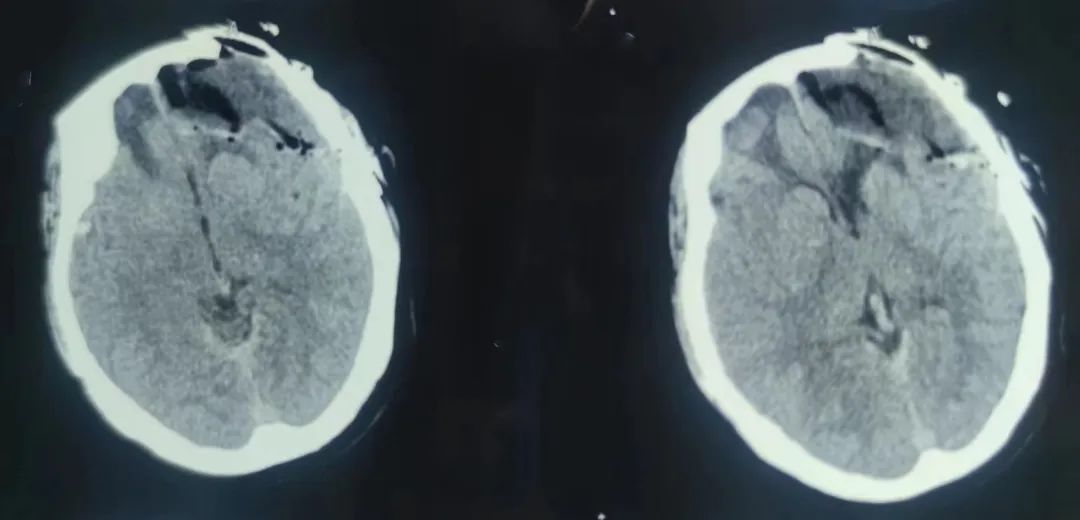

患者入院后完善顱腦癲癇序列磁共振、視頻腦電圖等相關(guān)檢查,確診患者為額葉癲癇(復(fù)雜部分性發(fā)作繼發(fā)全面強(qiáng)直陣攣發(fā)作),額葉失神發(fā)作。神經(jīng)外科副主任醫(yī)師王明義結(jié)合患者既往病史,發(fā)現(xiàn)其長期服用大劑量的抗癲癇藥物治療,但仍難以控制癲癇發(fā)作,考慮為藥物難治性性癲癇。對(duì)于藥物難治性癲癇,往往需要手術(shù)治療,而精準(zhǔn)定位癲癇病灶并切除是手術(shù)成功的關(guān)鍵。

與家屬充分溝通后,完善相關(guān)術(shù)前檢查,手術(shù)由癲癇外科專家王明義副主任醫(yī)師主刀,在麻醉科、手術(shù)室、影像中心、神經(jīng)電生理科、神經(jīng)外科等醫(yī)護(hù)人員的通力配合下,精準(zhǔn)定位了患者的致癇灶,用嫻熟的技術(shù)順利切除癲癇灶并對(duì)顱骨修補(bǔ)材料進(jìn)行了更換。術(shù)中患者神經(jīng)功能保護(hù)完好。